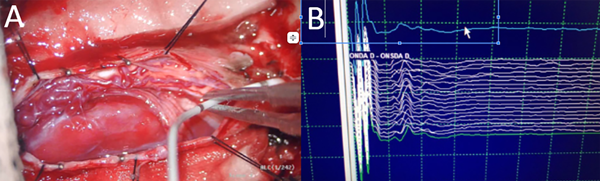

Fig 3. Caso 1. Colocación de monitoreo neurofisiológico sonda D (A); monitorización de onda D (B).

En todos los casos se planteó la misma estrategia de laminectomía y resección. Desarrollaremos a modo de ejemplo las características del tiempo quirúrgico utilizando el Caso Nº 1 (Figura 3).

Posicionamos al paciente en decúbito prono con soporte dorso lumbar. Se utilizó cabezal de Mayfield para fijar la cabeza. Se realizó incisión lineal desde C2 a C5. Se disecó tejido hipodérmico hasta ligamento vertebral posterior; se abrió la fascia muscular hasta exponer las apófisis espinosas y las láminas. Se procedió a realizar laminectomía C3-C5 y flavectomía C2-C6. La duramadre fue abierta en forma lineal. Se realizó monitoreo neurofisiológico con onda D. Se visualizó lesión voluminosa que desplazaba raíces y cordón medular a derecha de color gris-rosada, vascularizada que impresionaba nacer de raíz sensitiva C4 izquierda. Se colocaron en ambas aferencias arteriales en el polo superior, clips transitorios por 5 minutos sin cambios neurofisiológicos, continuando con la sección de ambas aferentes. Se luxó la lesión que quedó pendiente de vena arrosariada en cara posterior de la médula, la cual se coaguló y seccionó con remoción de la lesión en bloque.

El monitoreo neurofisiológico es de suma utilidad para permitir identificar déficits neurológicos intraoperatorios significativos y persistentes en el tiempo y, de esta manera, guiar al neurocirujano para lograr una adecuada resección y mejor evolución funcional del paciente.